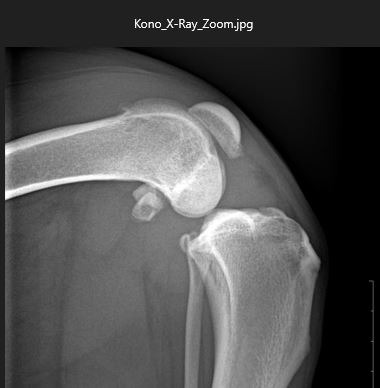

This is Kona, our sweet 20 month old Dalmatian-Labrador. In late August, she started limping. A trip to the vet and some x-rays later, she was diagnosed with torn cranial cruciate ligaments (CCL) in both hind legs. These are ligaments that hold the femur and tibia (upper and lower leg bones, respectively) in correct alignment and also stabilize the knee joint. As you can imagine, Kona is in a lot of pain, and is no longer able to walk normally, sit properly or engage in normal activity.

For large dogs (Kona weighs about 68 pounds) veterinarians recommend TPLO or Tibial Plateau Leveling Osteotomy, a surgery to stabilize the knee and allow for future normal and pain-free movement. [More info on TPLO-click here ] Due to her size and age, our vet recommended that the surgery be performed by a board-certified veterinary surgeon. TPLO surgery is very costly, between $7,000 - $10,000 per knee with a somewhat long recovery. Not treating the injury is not an option and would lead to more damage to the knee joints because of her size.